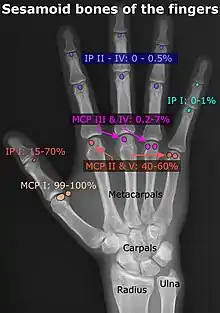

- Location and structure: Erica Chu, Donald Resnick. "MRI Web Clinic — June 2014: Sesamoid Bones: Normal and Abnormal". Retrieved 2017-11-04.

- Prevalences: Chen W; Cheng J; Sun R; Zhang Z; Zhu Y; Ipaktchi K; et al. (2015). "Prevalence and variation of sesamoid bones in the hand: a multi-center radiographic study". Int J Clin Exp Med. 8 (7): 11721–6. PMC 4565393. PMID 26380010. - ↑ "Poster Abstracts" (PDF). Association for Sports Medicine of Serbia (Udruženje za medicinu sporta Srbije). 2006. Retrieved 2017-11-03., citing: Natsis K.; Beletsiotis A.; Terzidis I.; Gigis P. "A study of the accessory bones of the foot. Incidence in the Greek population-clinical significance" (PDF).